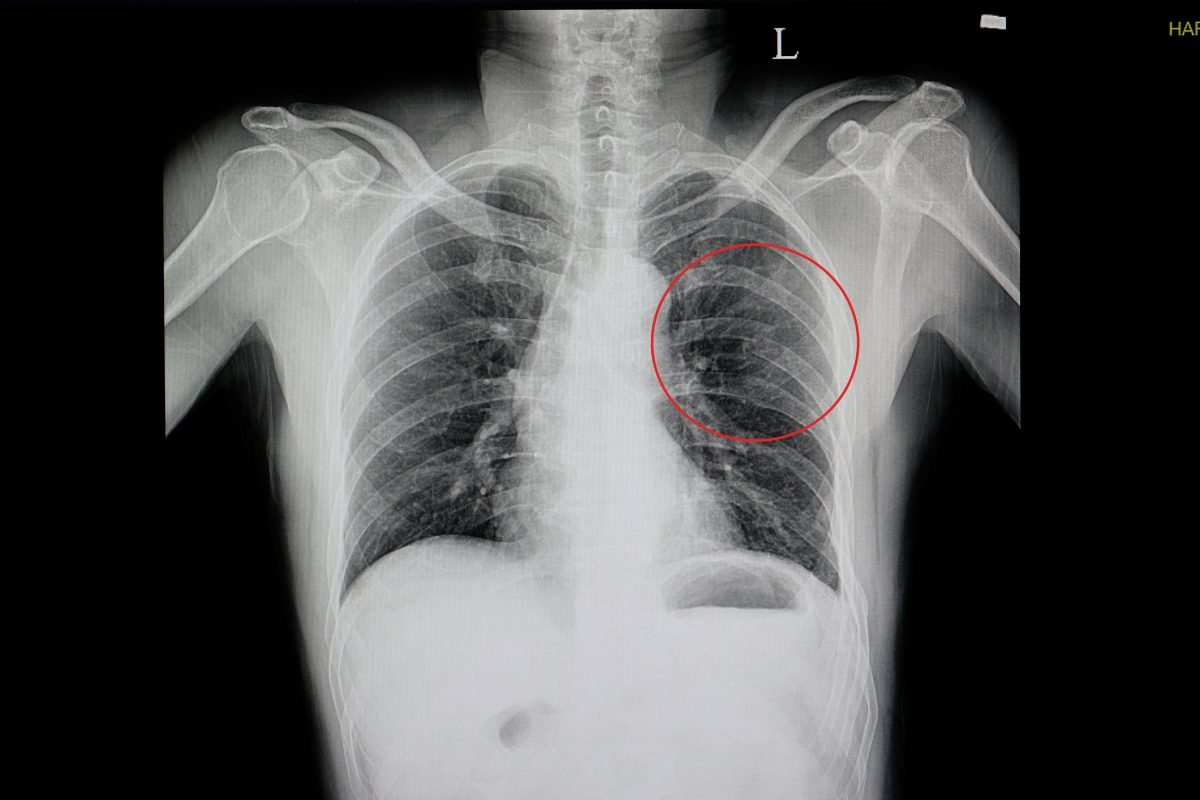

진단은 물론 X-ray 나 CT, bone scan 같은 영상검사로 하게 되지만

임상적으로 지속적인 minor 한 통증이 지속되며, 숨을 들이마시는 등의 흉곽을 팽창하는 조건을 보일 경우 통증이 악화되거나 재현될 수 있습니다.

골절이 생긴 후에 회복이 되는 경우에도 엑스레이에는 유합된 흔적이 남을 수 있습니다.